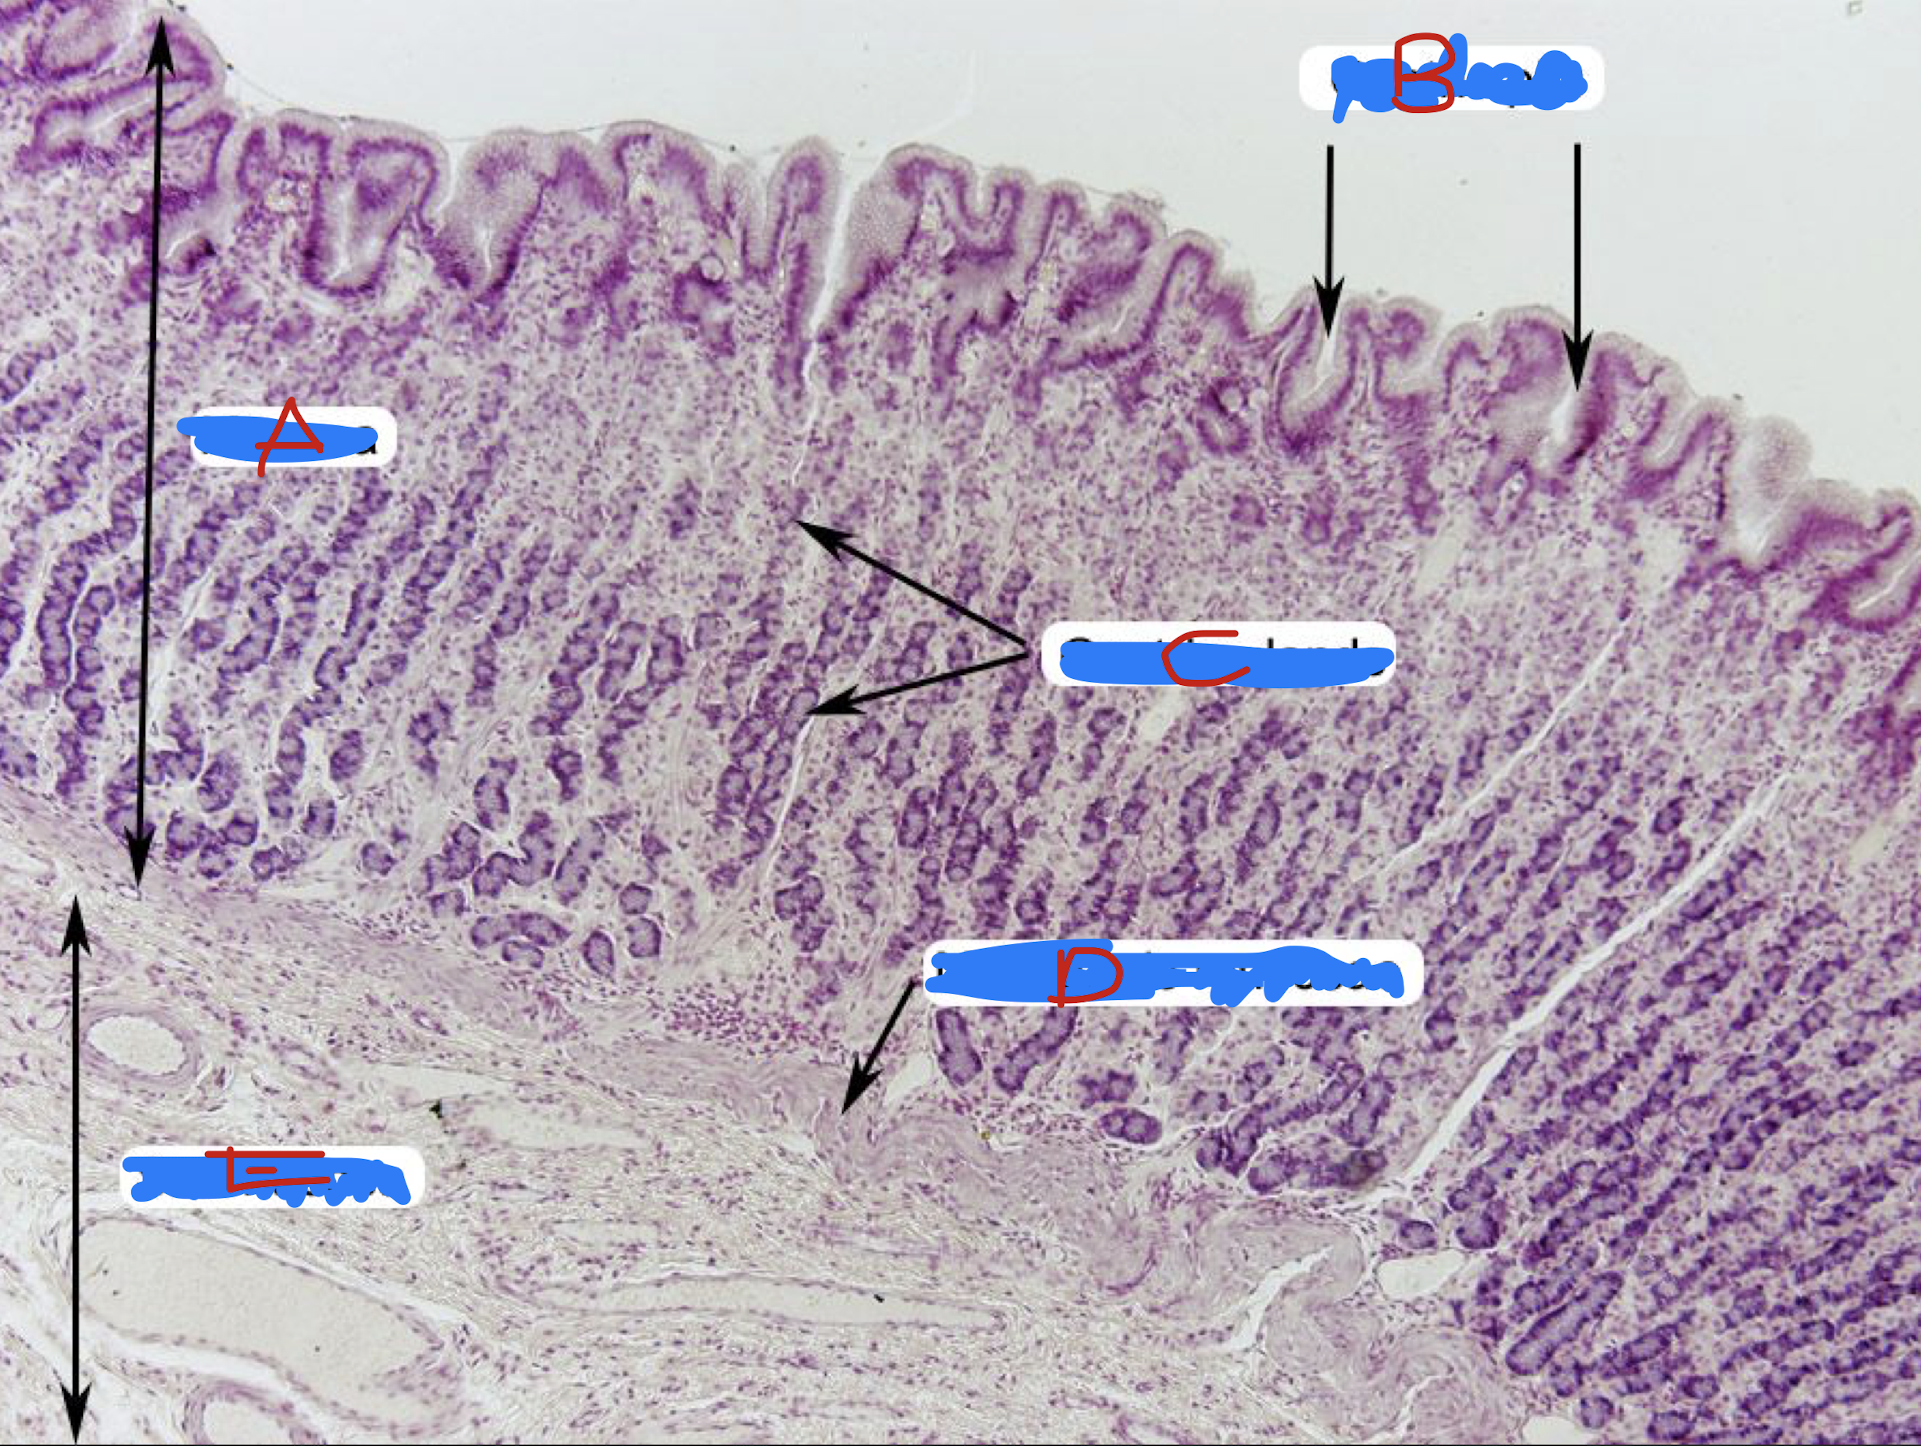

STOMACH

A: rugae

B: surface mucus and mucus neck cells

C: parietal or oxyntic cells

D: chief/principal/zymogenic cells

E: mucosal folds

F: submucosa

Identify the structure

A: mucosa

B: gastric pits

C: gastric glands

D: muscularis mucosa

E: submucosa